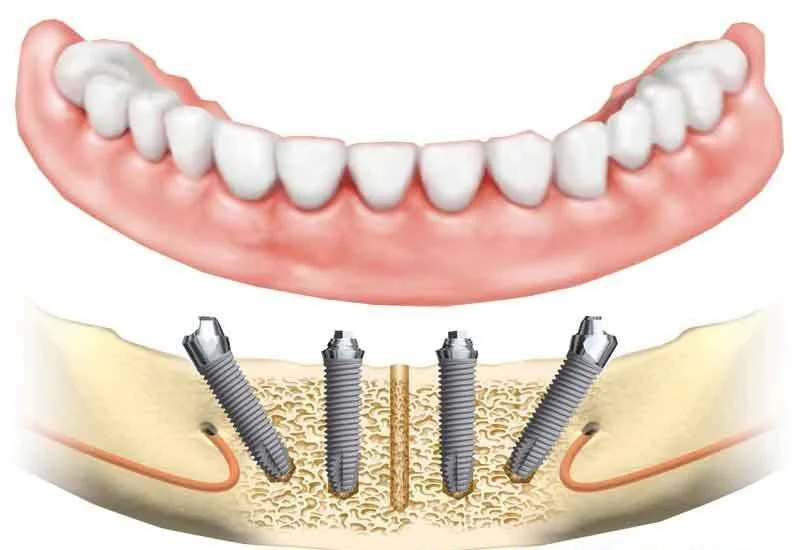

• Çoklu diş kayıplarında her kaybedilen diş için birer implant uygulanmaz. Onun yerine kaybedilen diş sayısına göre 4 veya 6 implant uygulanarak tüm çene diş eksiklikleri giderilir.

All-On-Four

• Tamamen dişsiz çenelerde zamanla fazlaca kemik erimesi oluşur. Kemik erimesinin fazlaca olduğu durumlarda çenelerin arka bölgelerinde implantları uygulayacak yeterli kemik bulunamayabilir.

• Bu tarz durumlarda çenelerin ön bölgelerinde olan sınırlı kemiğe 4 adet açılı implant yapılır. Bu implşantlardan ikisi açılı ikisi düz olarak yerleştirilir.

• All-On-Four tekniği olarak adlandırılan bu operasyonda özel implantlar ve protez parçaları kullanılır.